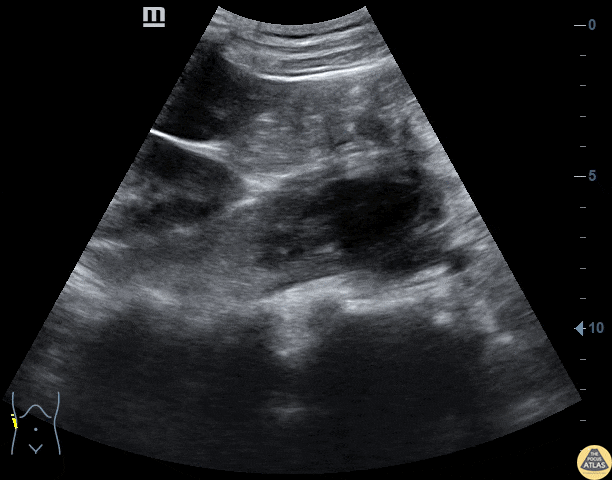

HIV+ male presents with flank pain and weight loss. Abdominal US demonstrates a psoas abscess inferior to the right kidney. Contributor: Niƫl van Hoving